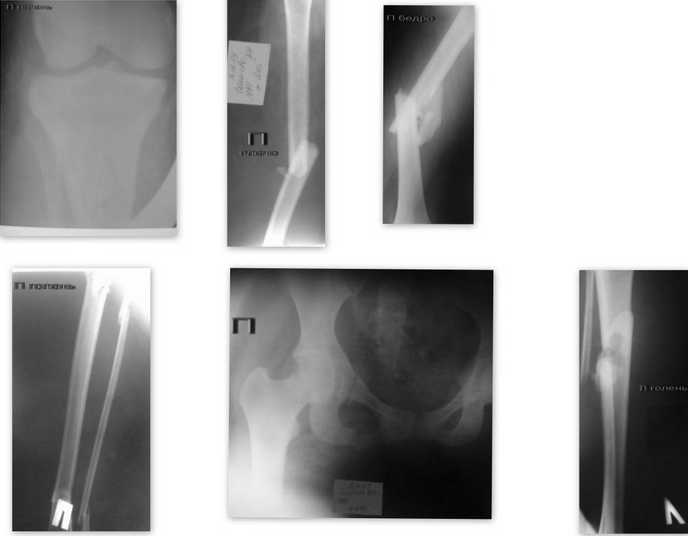

Ушиб г\мозга легкой ст.. З\перелом с\3 п\плеча, з\перелом с\3 п\бедра, з\двойной перелом п\голени, з\перелом с\3 л\голени, перелом лонной и седалищной костей справа, перелом 3 ребер и ключицы справа. Хотели на 3-й день заштифтовать ("родственники не захотелии"). В результате, сейчас больная находиться в травм. отделении на скелетном вытяжении. В сознании, стабильна, адэкватна, субфибрильная Т тела. Неоднократные беседы с родственниками "про неплохо бы заштифтовать теперь уже в отсроченном периоде", привели заботливых родственников на "ковер". В результате дан приказ прекратить всякие переговоры и определить больную по квоте в какой-нибудь фед. центр! О результатах доложить!